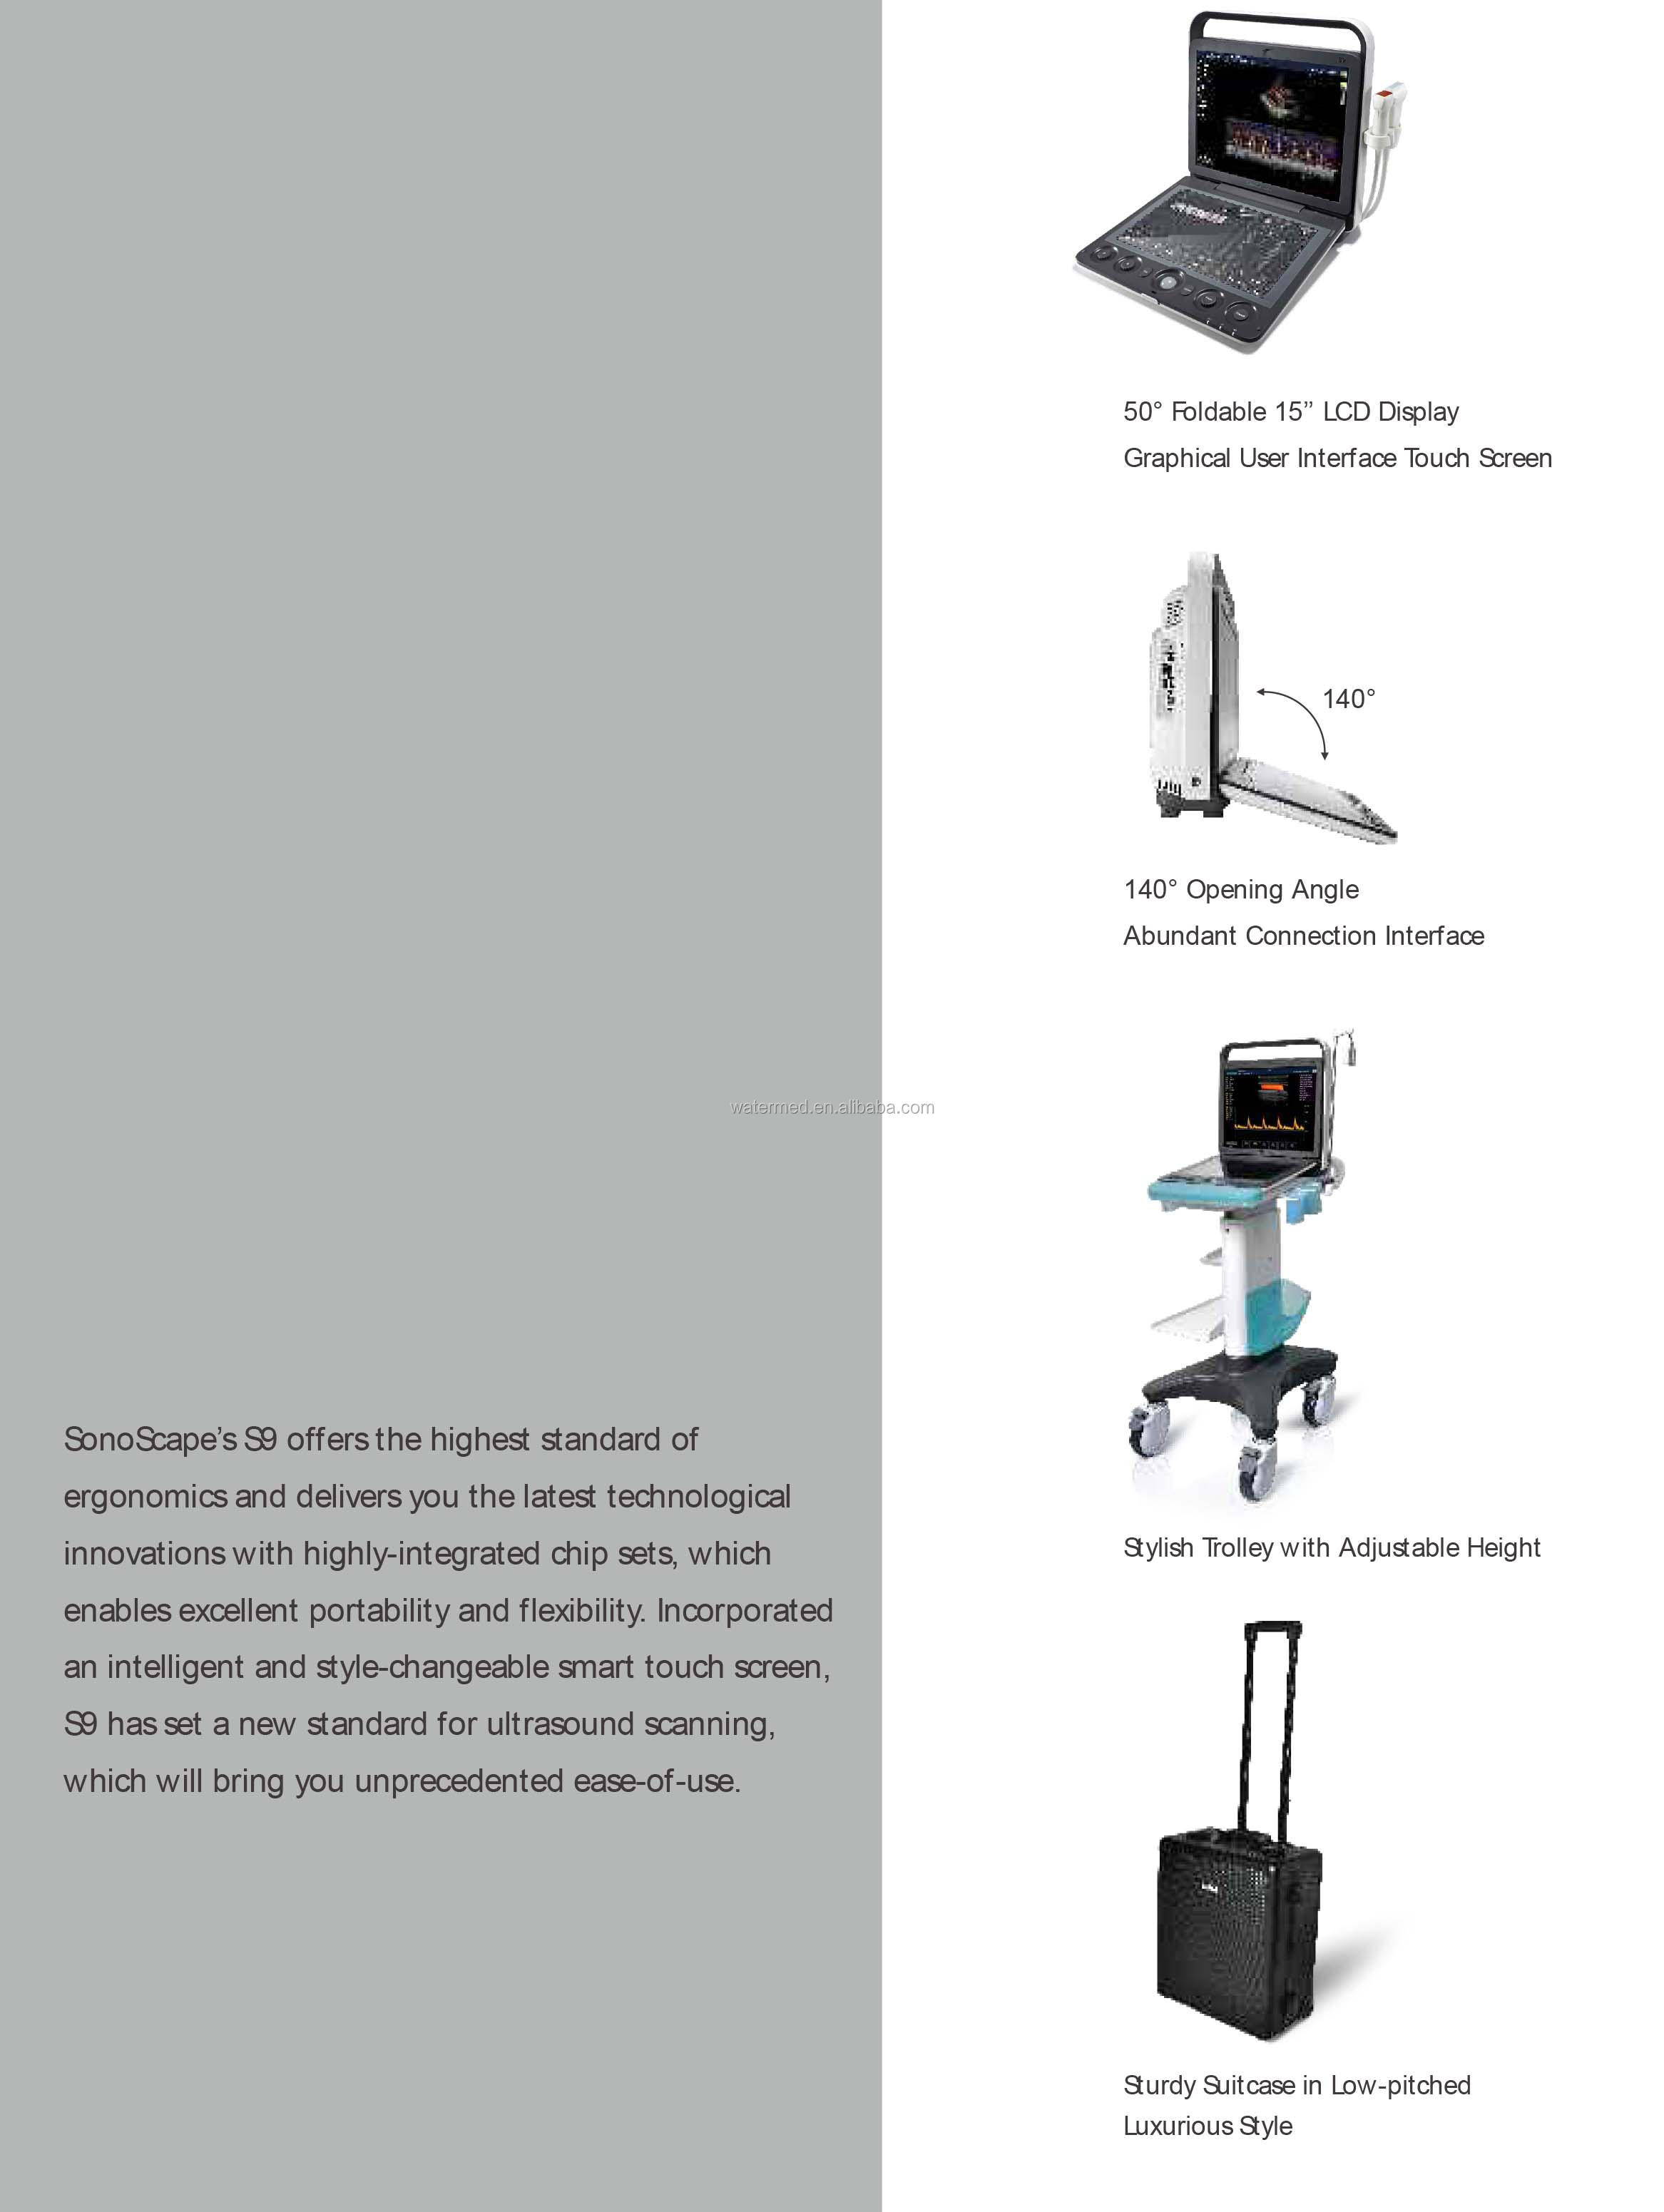

| payment terms: | L/C, Western Union, D/P, D/A, T/T, MoneyGram | touch screen: | 13.3 inches (135° variable) |

| Monitor: | 15" LCD (50°adjustable) | Double split mode: | B/C,B/M,B/DPI,B/PW,B/TDI |

monitor | 15" LCD (50°adjustable) | ||||||

touch screen | 13.3 inches (135° variable) | ||||||